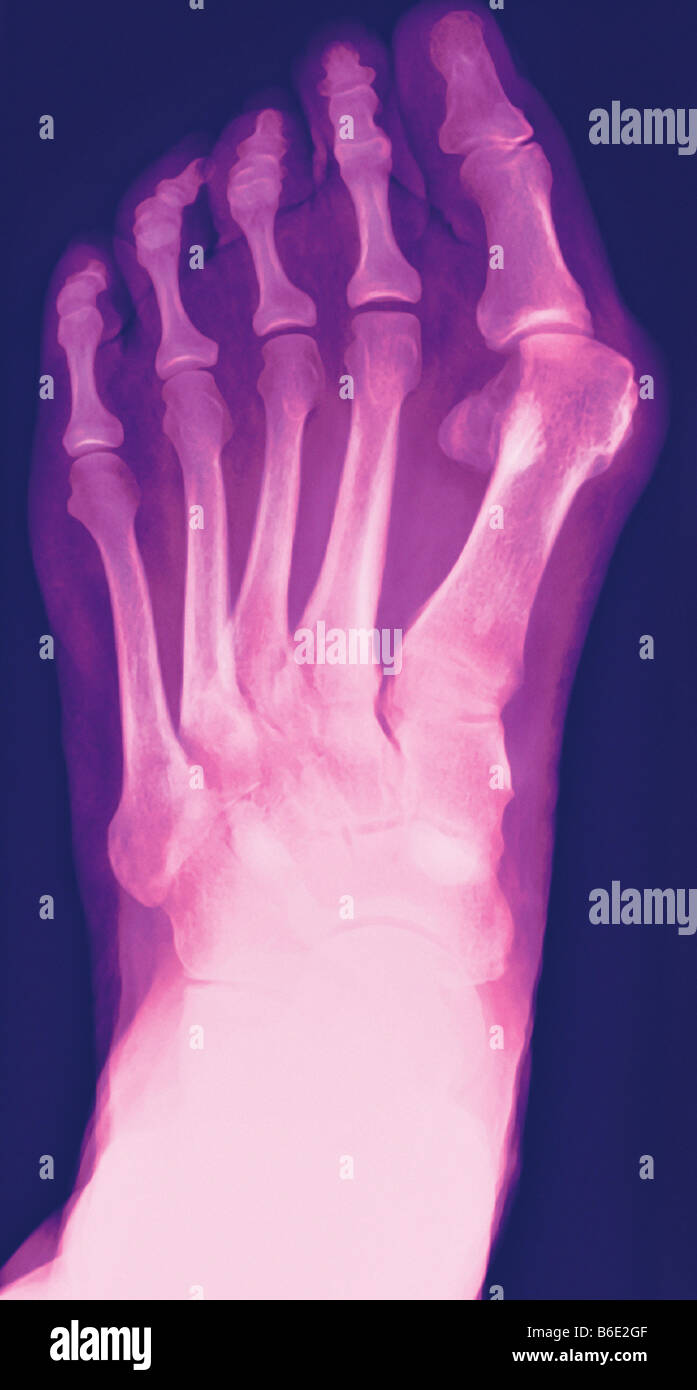

Bunion. Coloured Xray of a bunion (hallux valgus, upper right), the Foot Bunion Radiology Bunion, which is also known as the hallux valgus, refers to a constellation of symptoms including soft tissue swelling over the first metatarsophalangeal joint. A bunionette, also known as a tailor's bunion, metatarsus quintus valgus, or digitus quintus varus, is a bony prominence at. Halluces valgi) is a fixed abduction of the first metatarsophalangeal joint of the great toe. Hallux. Foot Bunion Radiology.